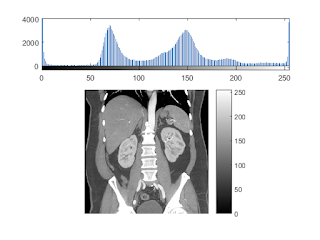

this matlab code provides some techniques and methods to view and identify organs of a CT image

The first method is to use histogram to segment the second method is to use color a CT image third method is filter.

plot histogram of the image

subplot(311); % plot to ensure a correct image is loaded.

imhist(I)

subplot(3,1,2:3);

imshow(I);

colorbar